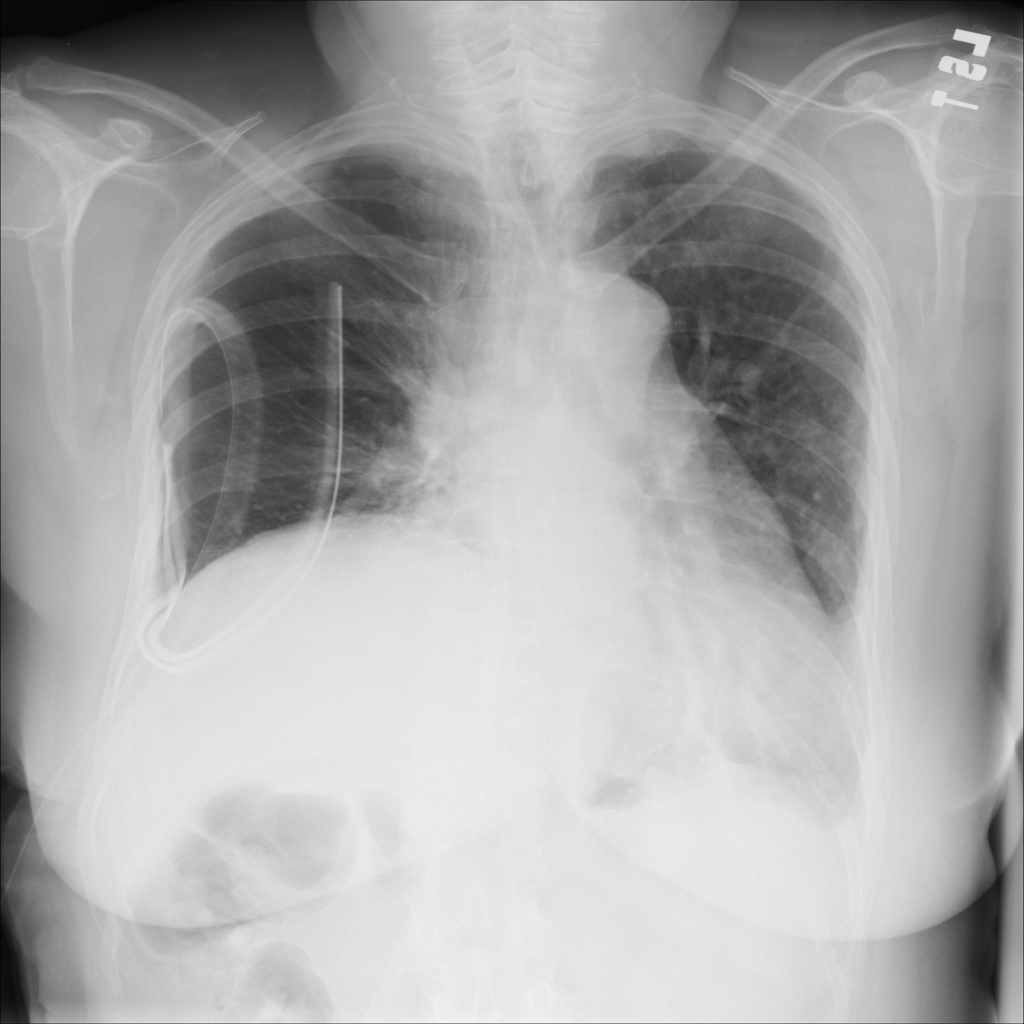

Mass

A mass is a larger focal opacity or lesion seen on the image. It is a descriptive finding that can have several causes and usually needs more imaging or clinical context to characterize.

PAT-D7A5 · IMG-000Mass

PAT-D7A5 · IMG-000

PA